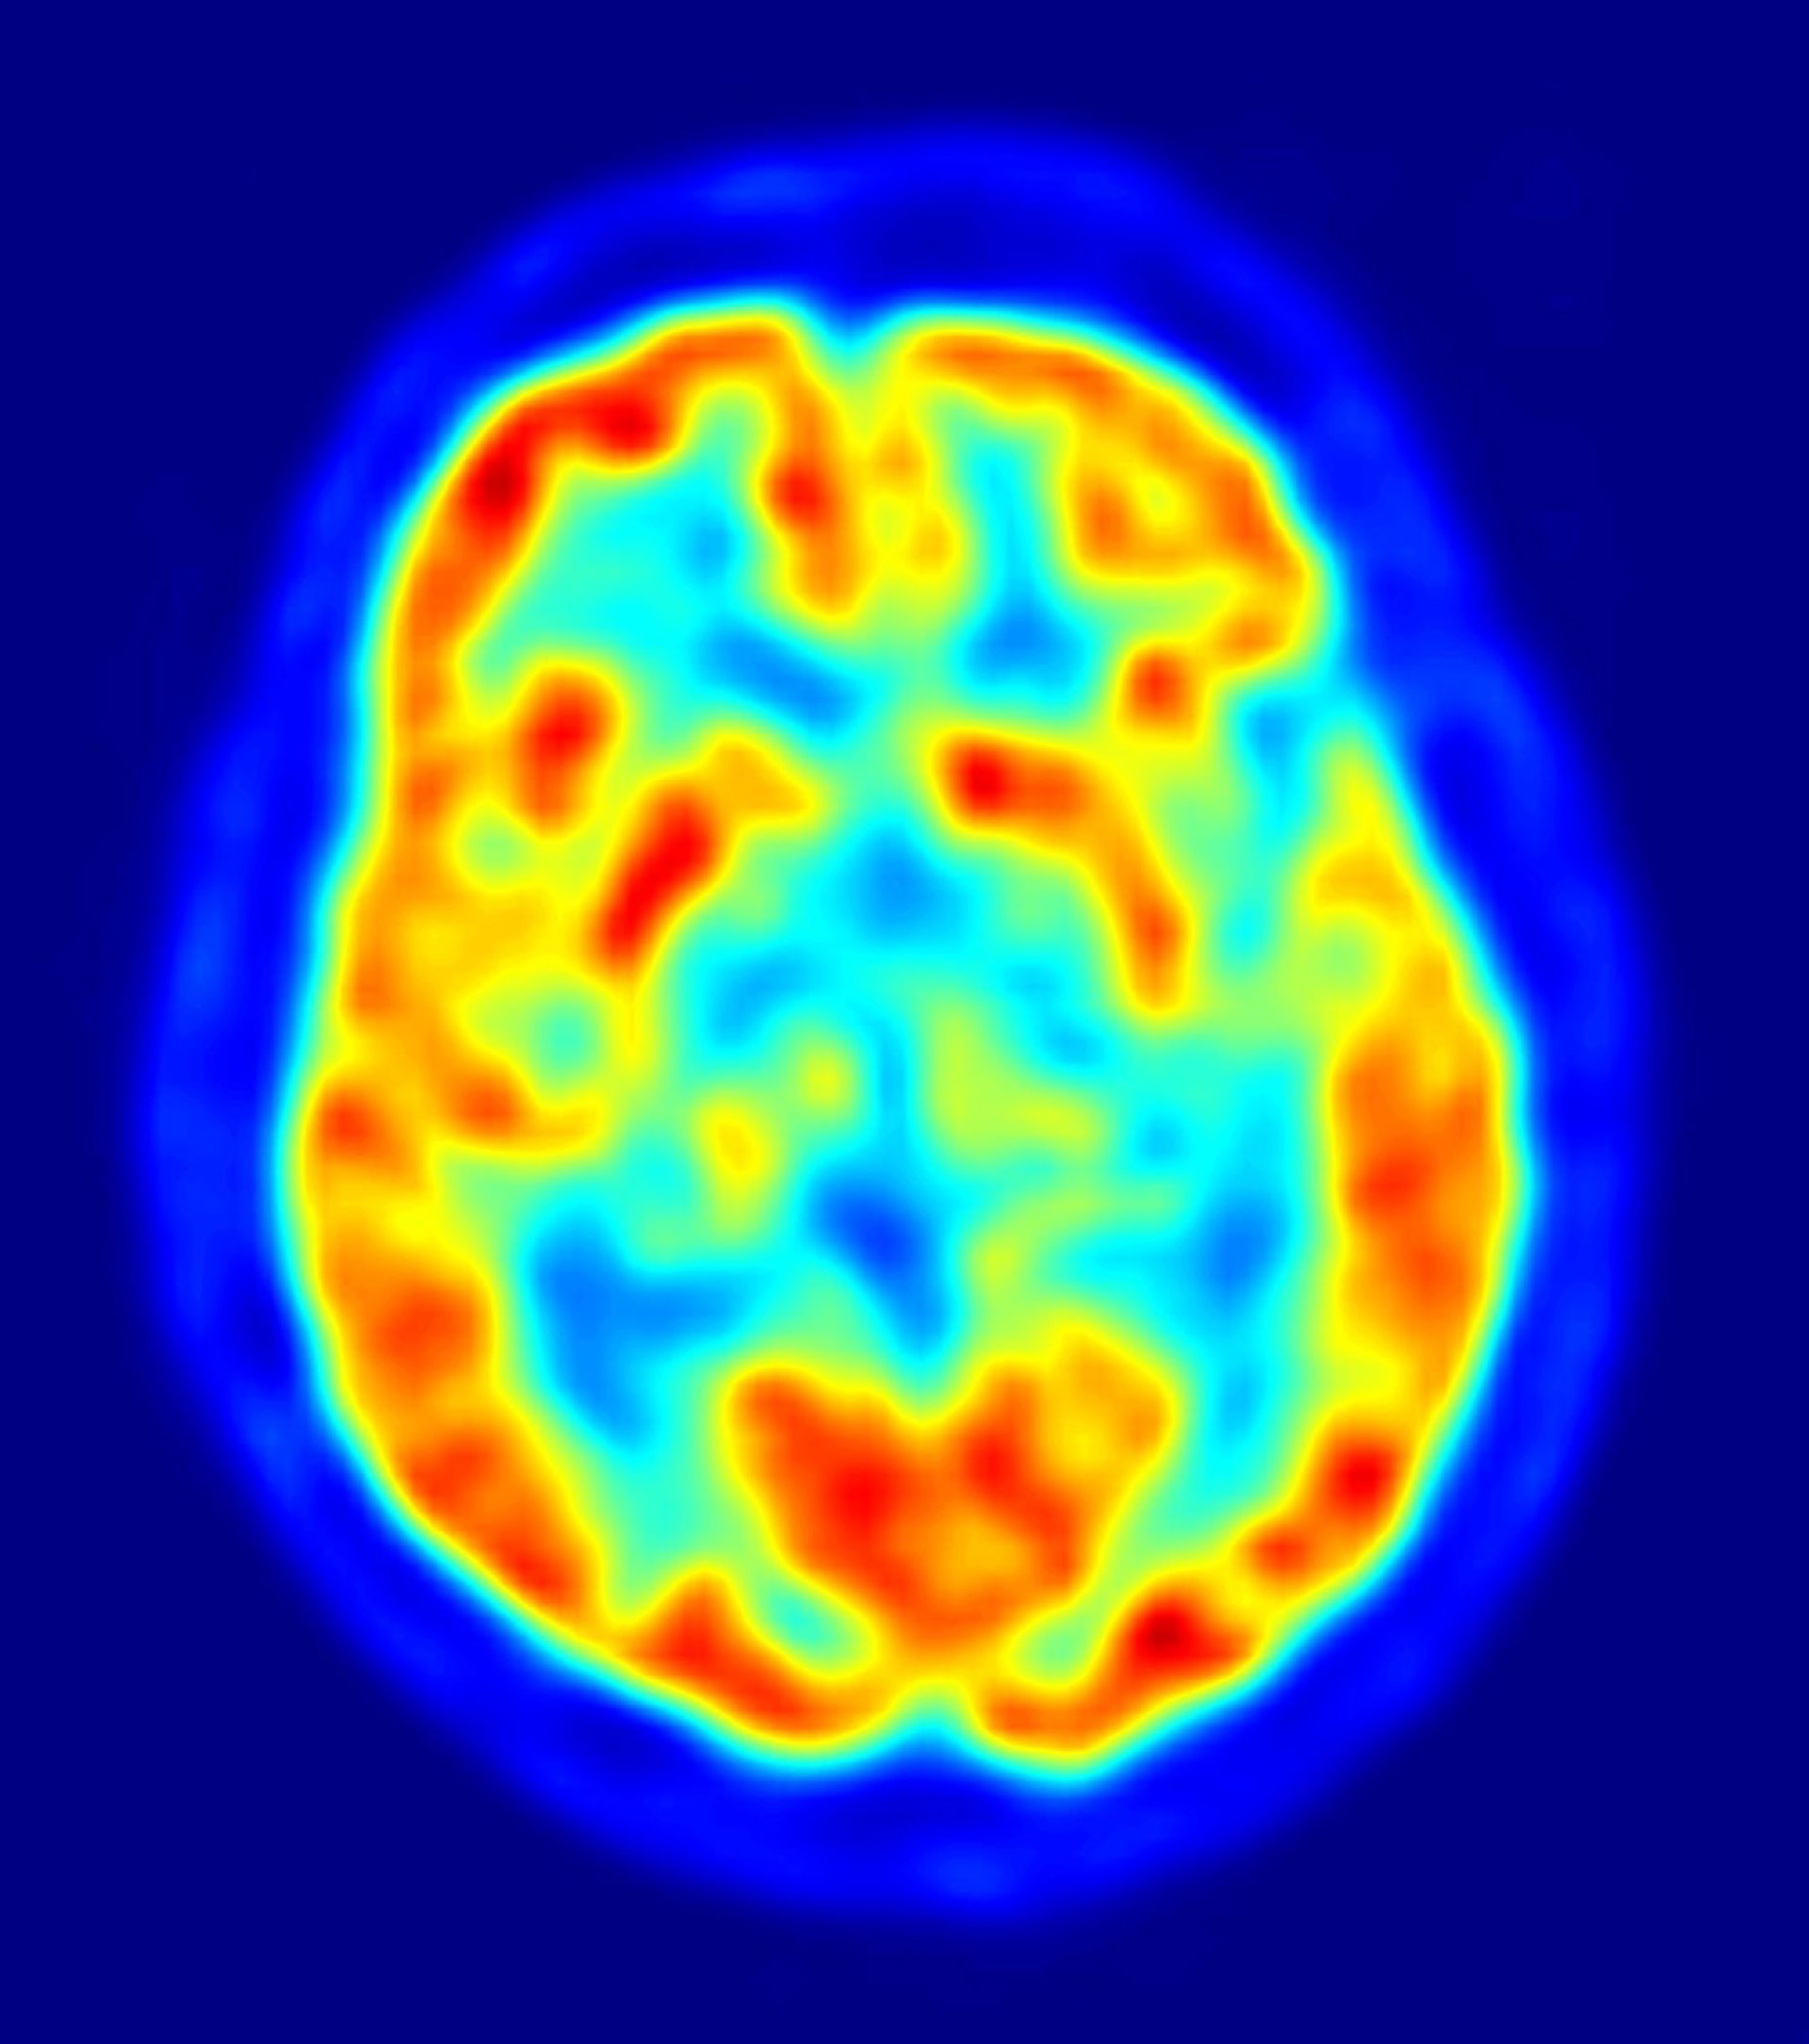

Investigadores de la Universidad de La Rioja, en colaboración con el Centro de Investigación Biomédica de La Rioja (CIBIR), están desarrollando un programa certificar diagnósticos a través del procesamiento de imágenes biomédicas para perfeccionar su estudio de cara a la detección del Alzheimer.

Los investigadores de la UR plantean la corrección de un programa concreto como un enunciado de un teorema matemático, así buscan que este se produzca en cada proceso. Como se trata de conseguir un diagnóstico veraz, recuerdan que el programa debe obtener los mismos resultados de que los médicos, lo que tiene su complicación si se tiene en cuenta que el médico interpreta la imagen y el ordenador analiza píxeles sin ninguna estructura.